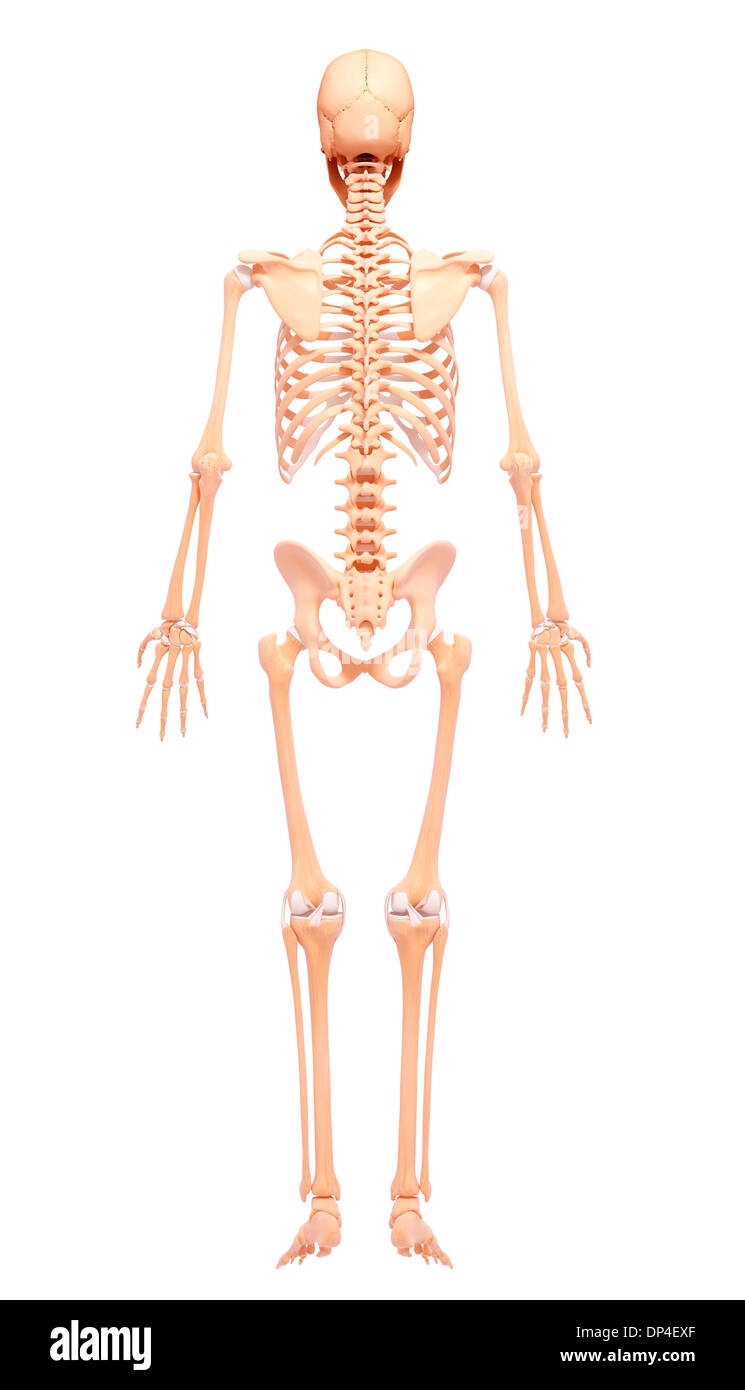

Human Skeleton, artwork Banque D'Imageshttps://www.alamyimages.fr/image-license-details/?v=1https://www.alamyimages.fr/human-skeleton-artwork-image65253063.html

Human Skeleton, artwork Banque D'Imageshttps://www.alamyimages.fr/image-license-details/?v=1https://www.alamyimages.fr/human-skeleton-artwork-image65253063.htmlRFDP4EXF–Human Skeleton, artwork